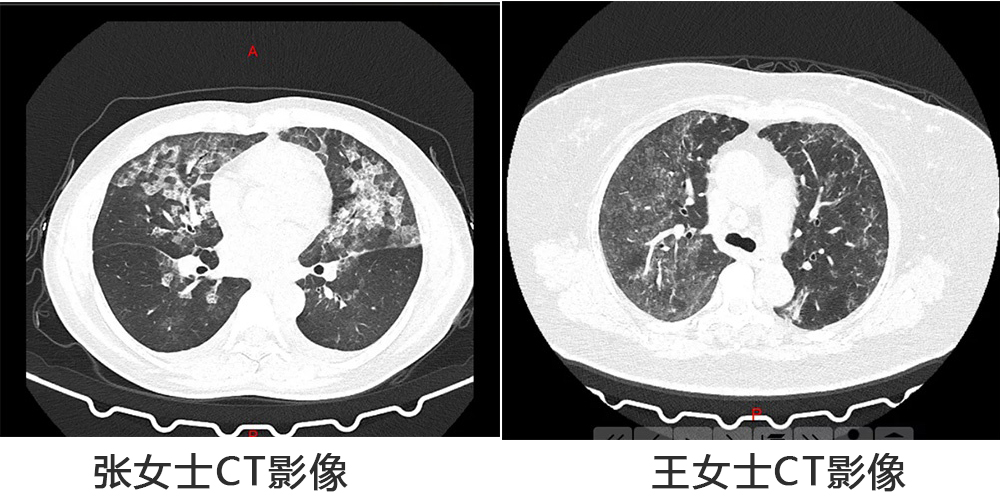

消毒过量,河南两女子肺部CT呈现毛玻璃状!

近日,河南郑州的张女士和王女士到医院就诊,结果胸部CT显示呈毛玻璃状,和新冠肺炎的CT表现基本一模一样,但是病人的接触史、症状表现,包括血象却不符合新冠的临床表现。经询问,才知道两人每天定时在家里喷洒高浓度的消毒液,并且长时间关闭门窗,导致…